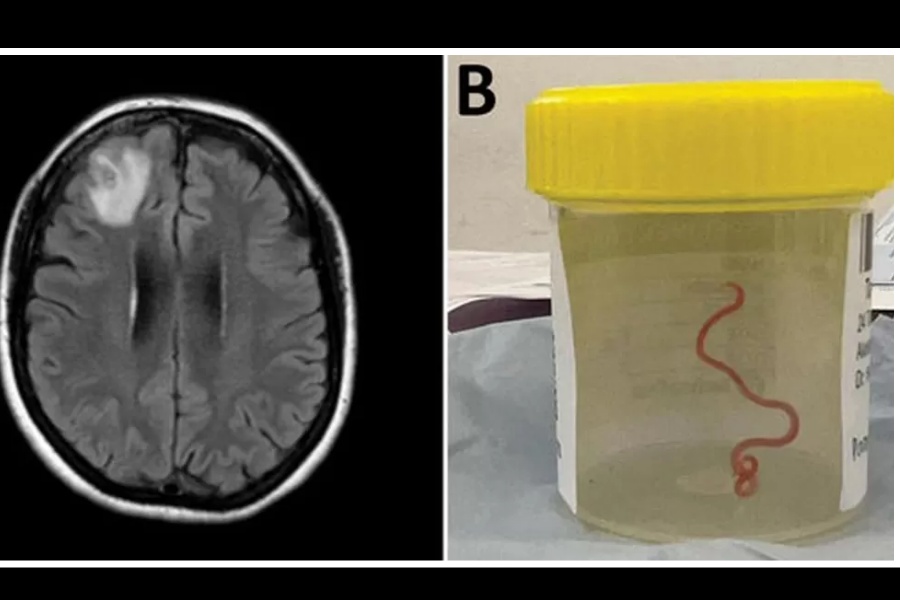

मस्तिष्कमा जीवित कीरा भेटियो

विश्वमा पहिलो पटक वैज्ञानिकहरूले एक अस्ट्रेलियाली महिलाको मस्तिष्कबाट ८ सेन्टिमिटर लामो जिउँदो कीरा निकालेका छन्। गत वर्ष क्यानबेरामा शल्यक्रियाका क्रममा बिरामीको घाइते फ्रन्टल लोबबाट धागो जस्तो किरा निकालिएको थियो। तर, यो शल्यक्रियाको पूर्ण रिपोर्ट यसै वर्ष सार्वजनिक भएको छ।

महिलाको शल्यक्रियामा संलग्न डाक्टरहरूले मस्तिष्कभित्र यति ठूलो जुका भेटिन्छ भनेर कल्पना गर्न पनि नसकिने बताएका छन्।

यी ६४ वर्षीया महिला केही महिनादेखि पेट दुख्ने, खोकी लाग्ने र राति पसिना आउने जस्ता समस्याबाट पीडित थिइन्। बिस्तारै उनी डिप्रेसन र एम्नेसियाको सिकार भइन्। सन् २०२१ को जनवरीमा उनलाई अस्पतालमा भर्ना गरिएको थियो । त्यहाँ स्क्यान गर्दा उनको मस्तिष्कको दाहिने भागमा एउटा अनौठो घाउ देखायो। तर त्यसको वास्तविक कारण भने सन् २०२२ को जुनमा बायोप्सी गर्दा मात्रै थाहा भयो।

अनुसन्धानमा खटिएका डाक्टरका अनुसार अस्ट्रेलियामा पाइने एक प्रकारको अजिंगर (कार्पेट पाइथन)मा ओफिडास्कारिस रोबर्टसी नामको त्यो जुका सहजै भेटिन्छ। ती महिलाले आफू बसेको स्थान नजिकै तालको छेउमा घाँस काट्ने क्रममा त्यो जुका समातिएको हुनसक्ने उनीहरूको भनाइ छ। यो घटनाले जनावरबाट मानिसमा सर्ने रोग र संक्रमणको बढ्दो जोखिमलाई औँल्याएको डाक्टरहरूले बताएका छन्।